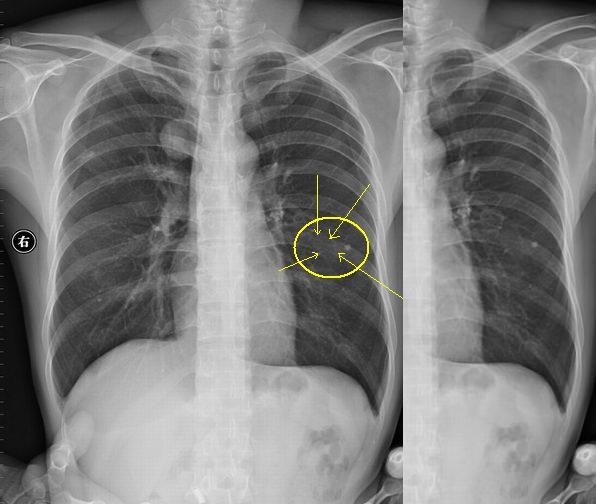

以下是引用sdqzwyx在2006-8-13 8:29:00的发言:[br][br]右上纵隔旁示类圆形密度增高影,边缘光整。[br]可以考虑:[br]1 首先排除体外异物:胸坠、衣服上的印花、口袋内圆形物件等。[br]2 肺内:若为肺内病变,肯定是良性的,肺结核球、囊肿、错构瘤等。[br]3 来源于纵隔、胸膜、或附近骨骼,病变与纵隔呈锐角,周围骨骼联系不太密切(见过一例来源于骨骼的骨软骨瘤重叠肺内),所以可能性不是太大。[br][br][本贴已被 sdqzwyx 于 2006-8-13 12:35:54 修改过]